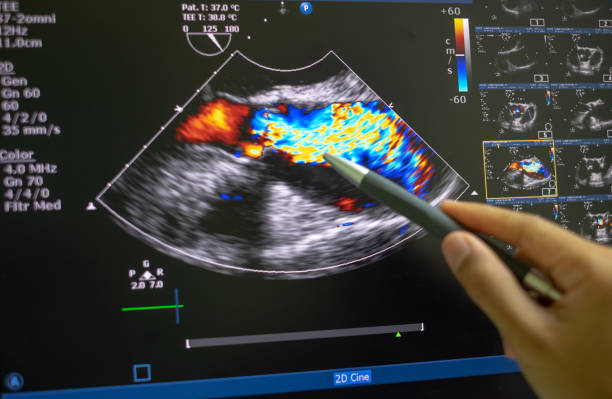

- Advanced diagnostic approaches, including bedside ultrasound in urgent care settings.

- Ultrasound imaging, for targeted, real-time diagnostics